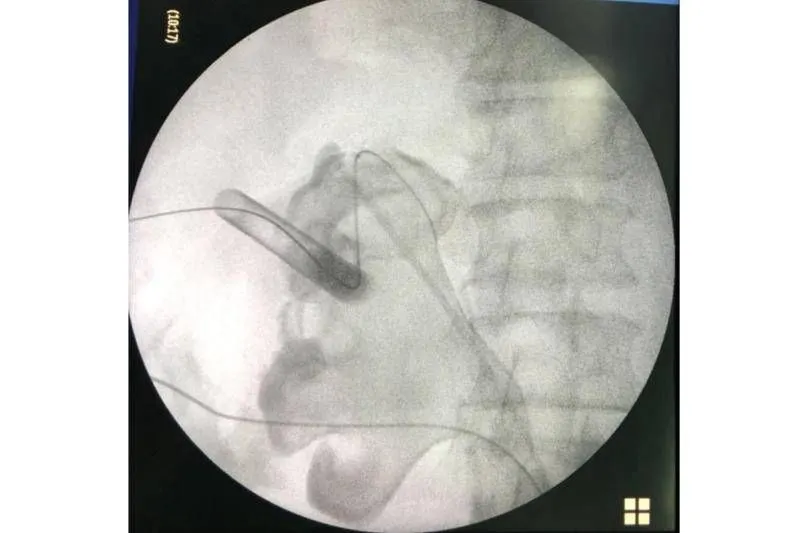

โดยสมาชิกเฟซบุ๊กคุณ Sirianan Prasit โดยนพ.ศิริอนันต์ ประสิทธิ์ นายแพทย์ชำนาญการพิเศษ รพ.ยะลา แผนกศัลยกรรมทางเดินปัสสาวะ ได้โพสต์ภาพพร้อมข้อความระบุว่า ของกลางที่พบในคนไข้รายหนึ่ง หลังจากที่ต้องทนทุกข์ทรมานกับอาการปวดหลังและอาการไตเสื่อม คงไม่ต้องบอกว่าคืออะไร ไม่อยากเป็นนิ่ว โปรดดื่มน้ำวันละ 6-8 แก้วต่อวันครับ นิ่วในไตใหญ่เบ้อเริ่ม ขอบคุณโครงการ #ก้าวคนละก้าว ที่นำเครื่องมือผ่าตัดนิ่ว มาสู่รพ.ยะลา

ขอบคุณภาพ : @Sirianan Prasit